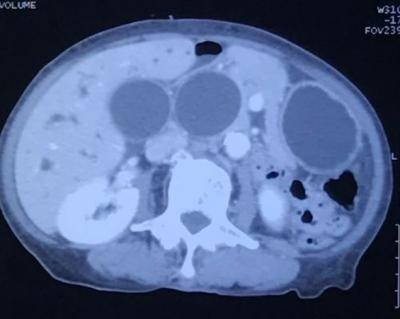

abdominal mass with haematuria

Figure 1: Contrasted computed tomography showing huge left homogenous and regular retroperitoneal lesion with peripheral enhancement on axial view